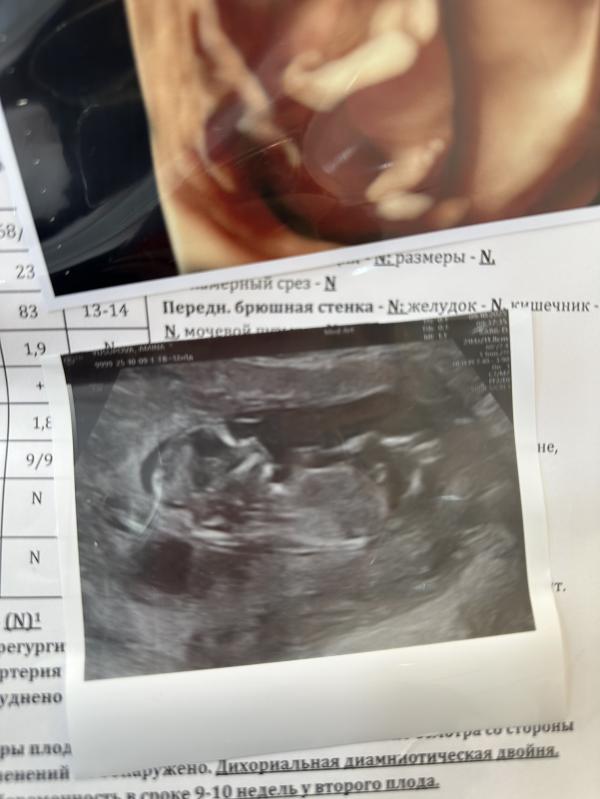

Сегодня была на узи,с малышом все хорошо😍❤️Как думаете кто ?

Если я вижу то что на фото это бугорок то мальчик

Я тоже по нему смотрела,потом думаю как будто на животе бугор,вдруг это пуповина

У вас двойня? Или что там написано в конце ?😅